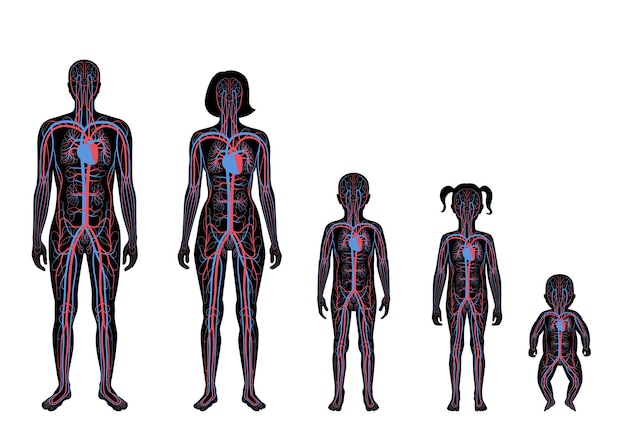

Human Arterial And Venous Circulatory System Anato 21139506

14/11/2025

ร่างกายมนุษย์